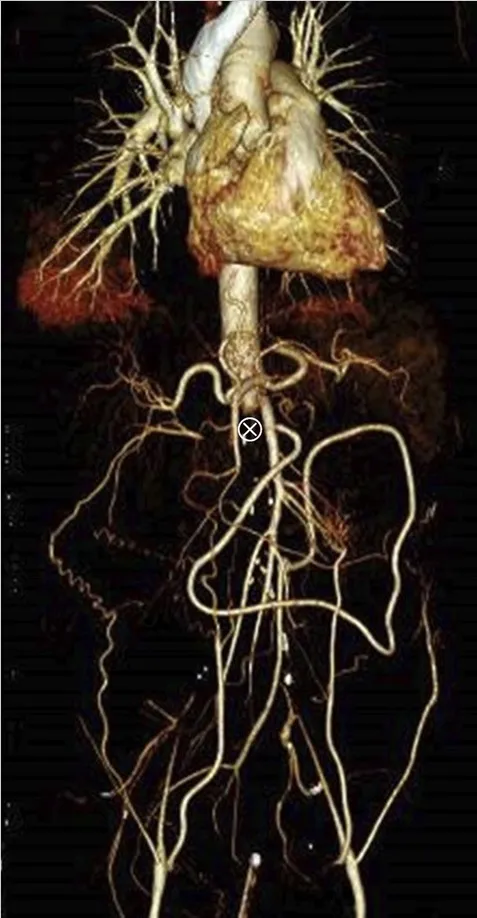

Realizado USG renal com Doppler que mostrou ecogenicidade e tamanho renal normais, mas sinais de oclusão aórtica na emergência da artéria mesentérica superior, o que foi confirmado por tomografia computadorizada com contraste (Figura 1).

A TC também revelou importante circulação colateral na parede abdominal, permitindo suprimento sanguíneo suficiente para os membros inferiores. Apenas o rim esquerdo mostrou captação residual de contraste (Figura 1), sugerindo rim direito isquêmico.

TC com contraste (reconstrução 3D) mostrando oclusão aguda da aorta justa-superior da artéria mesentérica. (A) Oclusão aórtica justa-superior à artéria mesentérica (marcada com um ⊗) juntamente com vasos colaterais na parede abdominal (B) Rim esquerdo com realce de contraste e rim direito sem realce sugerindo falta de perfusão renal.